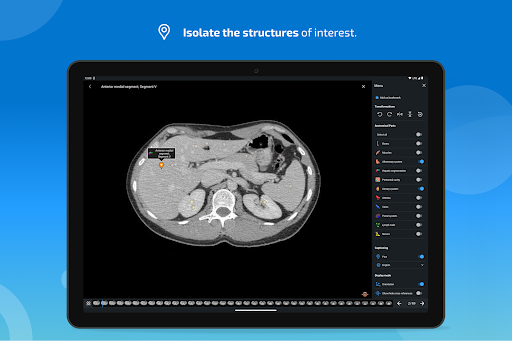

e-Anatomy memiliki lebih dari 26.000 gambar yang berisi serangkaian gambar dalam tampilan aksial, koronal, dan sagital serta radiografi, angiografi, gambar diseksi, bagan anatomi, dan ilustrasi. Semua gambar medis diberi label dengan cermat, lebih dari 967.000 label tersedia dalam 12 bahasa termasuk Terminologia Anatomica Latin.

- Ketuk label untuk menampilkan struktur anatomi

- Anda sekarang dapat menyembunyikan struktur satu per satu (tombol baru di dalam tampilan deskripsi) dan menampilkannya lagi di menu sebelah kanan